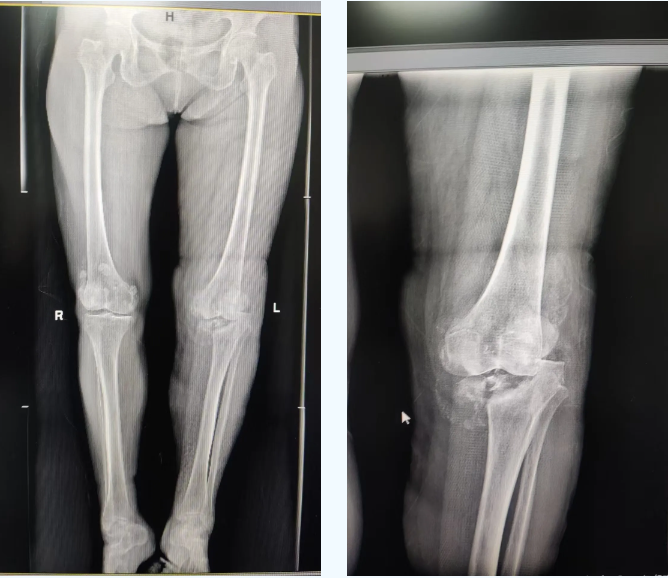

该患者长期饱受膝关节剧痛和活动受限困扰,生活质量严重下降。入院后经系统检查,确诊为梅毒性膝关节炎。此病本就罕见,加之患者膝关节已遭严重破坏,传统疗法难以奏效,关节置换成为唯一有效选择。然而,患者合并梅毒感染的特殊情况,使得手术面临极高的感染风险、复杂的免疫反应等难题,且国内外可借鉴的成功案例极为有限。面对如此复杂的病情,我院骨关节科迅速启动多学科会诊,联合院内皮肤科、感染科、检验科、麻醉科专家,并特邀四川大学华西医院专家进行远程会诊。团队深入研讨病情,整合各学科优势,为患者量身定制了精准的治疗方案。

术中,骨关节科医疗团队在手术过程中严格遵循既定方案,凭借精湛的技术和丰富的临床经验,小心翼翼地对患者受损膝关节进行清理、修复并植入了铰链式人工膝关节。手术过程精准高效,历时约 2 小时,成功克服多重技术难关。